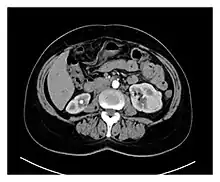

Preoperative contrasted CT scans of the patient, showing multiple bilateral kidney tumors, with diameters ranging between 1 and 5 cm. Radiologically, most of the tumors have malignant characteristics due to their hypervascularity and radiopaque enhancement.